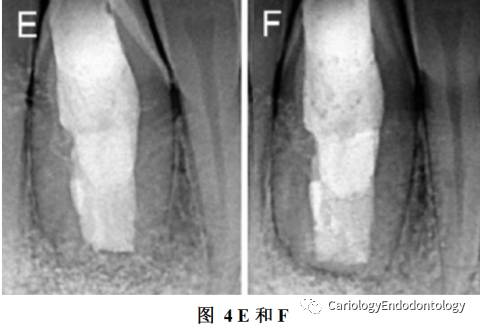

7、一周后,拆除缝线复查X线片,见图4 E

86个月后复查X线片。见图4 F